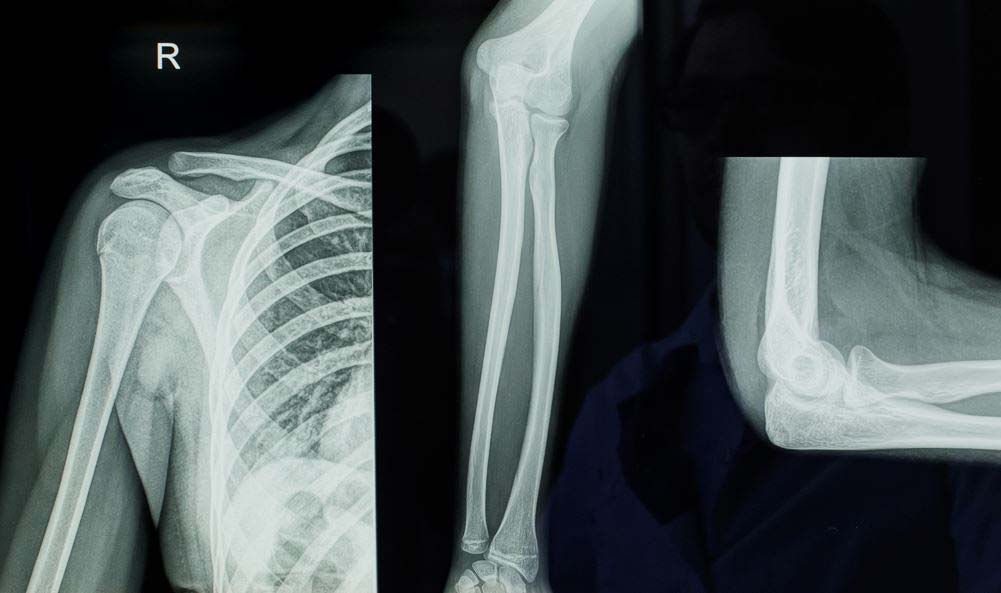

보통 X-ray로 손 뼈를 검사해 골연령을 측정하지만, 사춘기 시기에는 손 뼈의 변화가 뚜렷하지 않아 정확한 골연령을 측정하는 데 한계가 있다. 팔꿈치는 사춘기 동안 뚜렷한 변화를 보여 사춘기 환자를대상으로 골연령 평가를 할 때는 팔꿈치 골연령이 더 도움이 된다.

고려대 안산병원 영상의학과 최가영 교수 연구팀은 팔꿈치 측면 엑스레이 영상과 인공지능 모델을 이용한 사춘기 팔꿈치머리 뼈돌기 골연령 평가를 개발했다. 연구팀은 소아청소년 환자들의 팔꿈치 X-ray 5000장 이상을 분석해 기존 팔꿈치 골연령 평가방법의 제한점을 보완한 새로운 팔꿈치 골연령 평가기준을 제시했다. 고려대 안산병원 함성원 연구교수와 협업으로 인공지능 딥러닝 모델을 개발해 사춘기 팔꿈치 골연령 평가를 보다 정확하고 쉽게 할 수 있는 방법도 개발했다.

이번에 최가영 교수팀이 제시한 팔꿈치머리 뼈돌기 골연령 평가방법은 기존 평가방법과 비교해 높은 신뢰도를 보이면서도 팔꿈치 측면 X-ray 1장만을 필요로 한다. 또 더 다양한 팔꿈치 모양에 대해서도 골 연령을 평가할 수 있다. 팔꿈치머리 뼈돌기 골연령 평가를 위한 인공지능 모델도 최소한의 오차와 높은 정확도를 보여주었다.

최 교수는 "팔꿈치머리 뼈돌기를 이용한 새로운 팔꿈치 골연령 평가방법은 신뢰도도 높고 판독하기에도 직관적이고 간편하다"며 "팔꿈치 전후와 측면 X-ray 2장이 필요했던 기존 검사 방법과 달리 측면 X-ray 1장만 있어도 돼 더 간편하고 경제적이면서도 정확한 방법"이라고 했다.